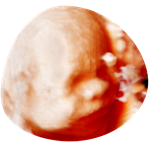

3/4D echo

Een bijzondere echo waarbij jouw ongeboren kind haarscherp en realistisch in beeld wordt gebracht. Je ziet niet alleen de contouren, maar ook het volume van je baby. Heeft hij/zij bolle wangetjes en op wie lijkt hij/zij eigenlijk? Soms zie je ook echt al de mimiek tijdens de echo: boos kijken, lachen, pruilen of even gapen…

€90 (30 minuten)